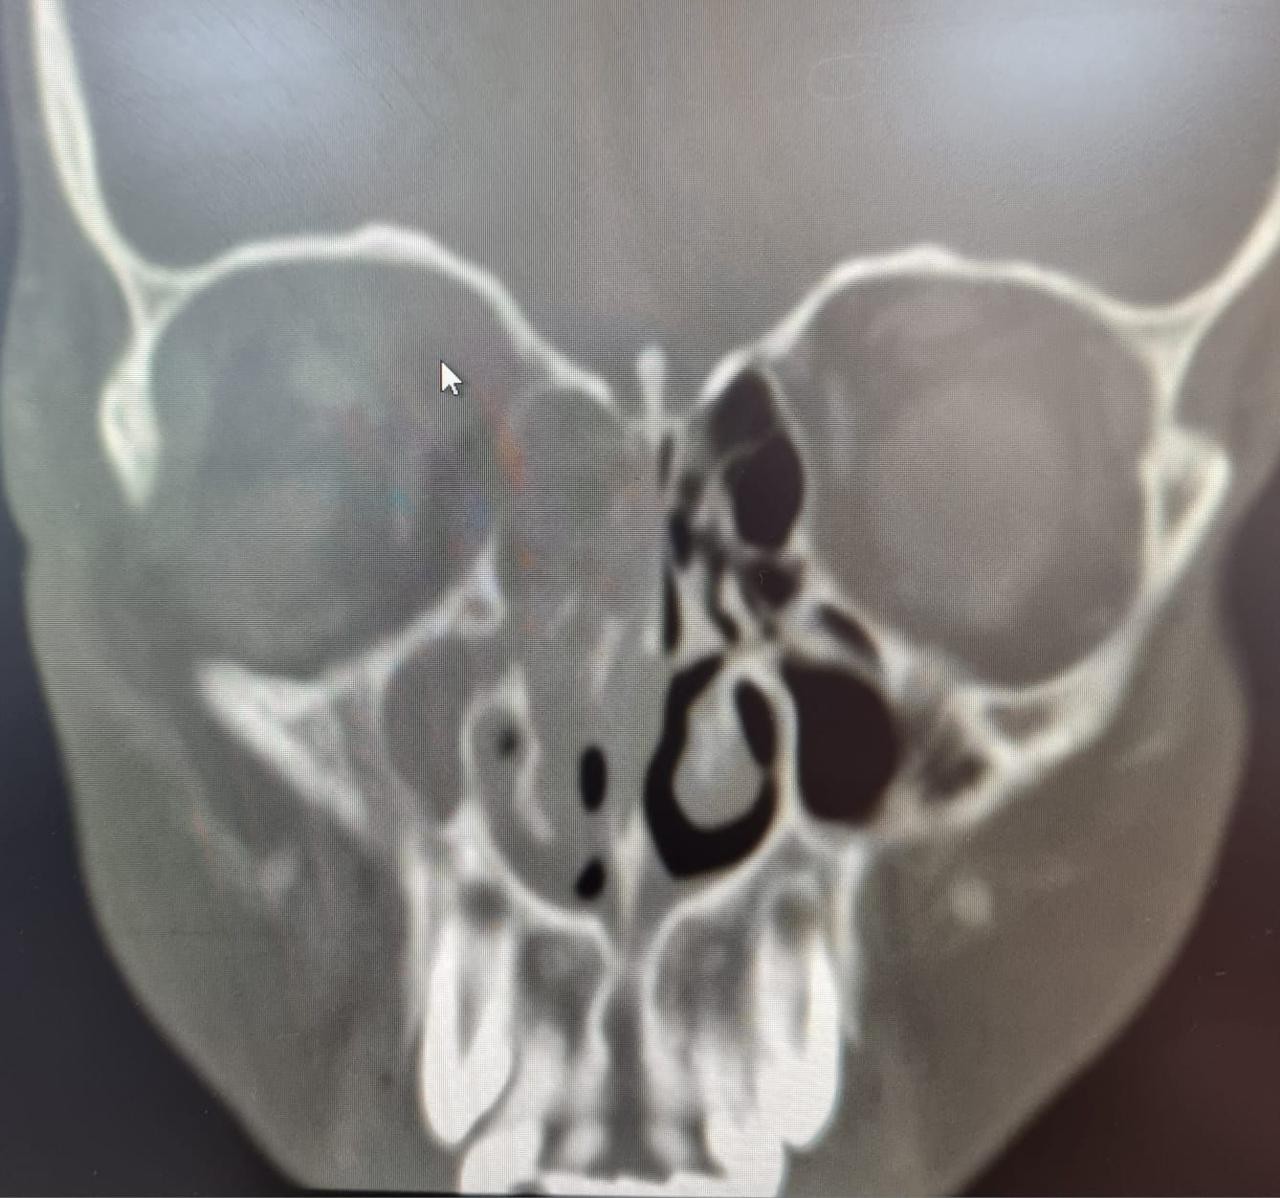

وأكدت الصحة في جدة أن المريض حضر إلى طوارئ مستشفى الملك عبد العزيز كحالة انقاذ عضو يشتكي من ألم حاد و احمرار و انتفاخ شديد في العين اليمني منذ خمسة أيام ، و تم عمل الفحوصات و الأشعة المقطعية اللازمة التي أظهرت التهاب شديد في الجيوب الأنفية من الجهة اليمني أدت إلى وصول خراج (صديد) لمقلة العين اليمني.

وبينت أن الفريق الطبي المعالج قرر إجراء تدخل جراحي عاجل وإجراء عملية دقيقة بالمنظار للجيوب الأنفية و تنظيف كامل لكل الاحتقانان و الالتهابات و الخراج (الصديد) لجميع الجيوب الأنفية للجهة اليمني و الجهة الداخلية للعين اليمني ، ليتم بعدها نقل المريض لقسم التنويم ومتابعة الحالة من قبل الفرق التمريضية لحين استقرار الحالة وخروجها بالسلامة من المستشفى.